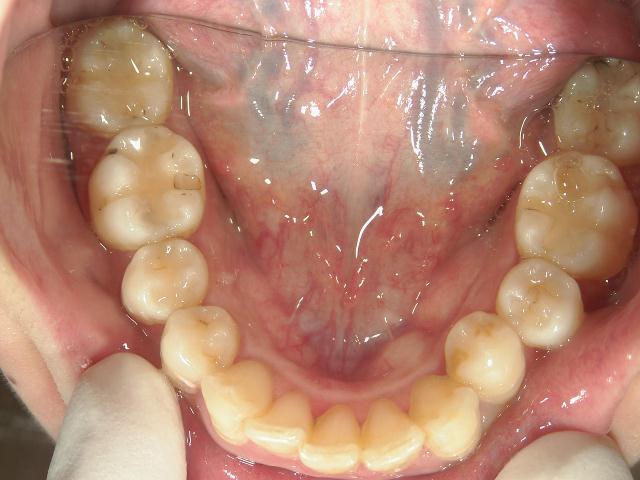

矯正歯科 治療後 上顎

矯正歯科 治療後 下顎